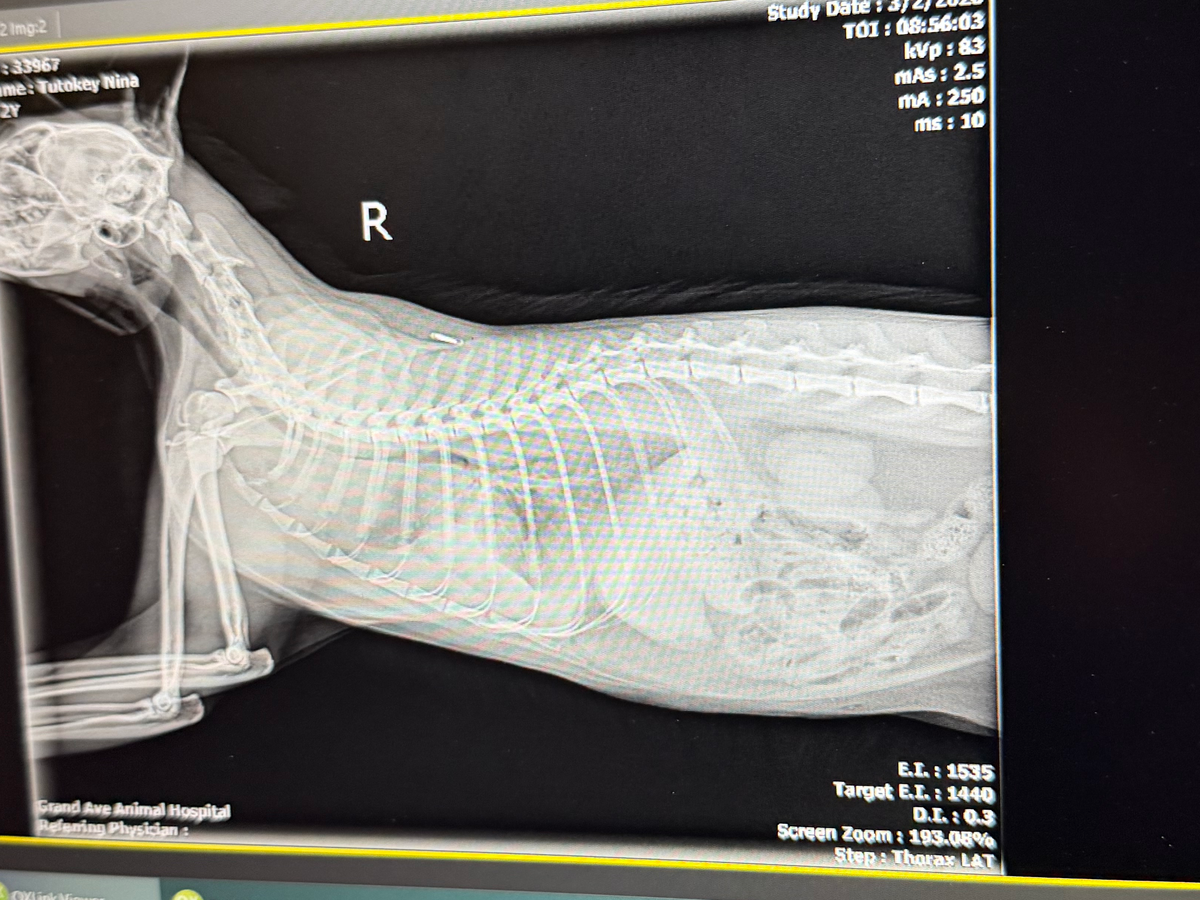

Unfortunately she was admitted to the emergency vet yesterday with pyothorax (septic fluid filling her lungs). She is in critical care & has had two procedures to remove the fluid. We were hoping she’d be able to come home today but unfortunately the lung filled up again & they had to do another drainage.